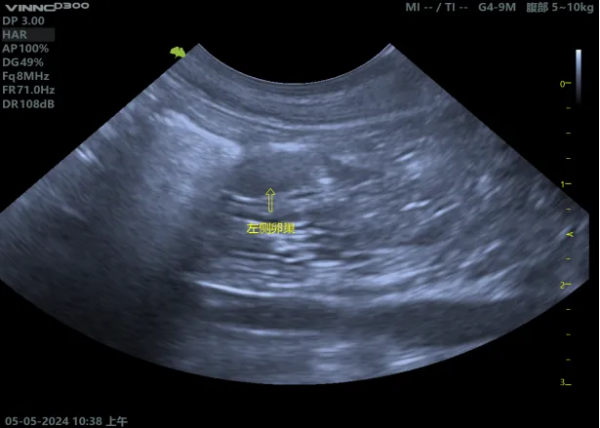

04【超声下表现】 (1)正常子宫影像 (2)子宫残端积液影像 (图片来源:Mattoon, J. S., Sellon, R. K., & Berry, C. R. (2020). Small animal diagnostic ultrasound (4th ed.). Elsevier Saunders.)

05【诊断】 (1)病史:有绝育手术史,之后出现上述症状。 (2)体格检查:腹部触诊可能摸到腹内的团块。 (3)影像学检查: ① 超声:这是首选的、最具诊断价值的方法。可以清晰地看到膀胱附近有一个充满液体的囊状结构(子宫残端),并能评估其大小、壁的厚度和内容物性质。 ② X光:如果积液量很大,可能在X光下看到一个软组织密度的团块影,但不如B超直观。 (4)血液检查: ① 血常规:如果发生感染/蓄脓,白细胞会显著升高。 ② 激素水平检测:检测血清中的孕激素或抗穆勒氏管激素(AMH)水平,可以确认是否存在有功能的卵巢组织残留(即OSS)。这是诊断OSS的金标准。 ③ 阴道细胞学检查:如果有阴道分泌物,可以检查分泌物中的细胞类型,判断是否存在感染和激素影响。